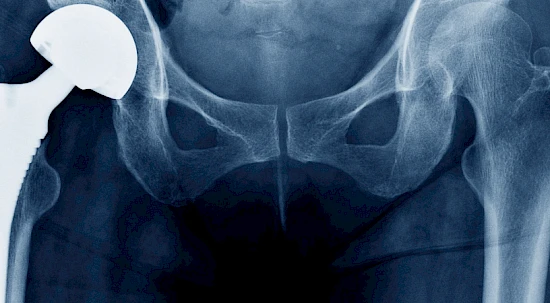

Das Fachgebiet der Orthopädischen Chirurgie und Traumatologie des Bewegungsapparates befasst sich mit dem Spektrum der Entwicklungsstörungen, Erkrankungen sowie Verletzungen des Bewegungsapparates. Unsere Chirurgen und Chirurginnen der Orthopädie sind auf diverse Operationen spezialisiert, unter anderem Hüftprothesen, Schulterchirurgie oder Handoperationen.

Zum Bewegungsapparat zählen die Knochen, Muskeln, Gelenke, Sehnen und Bänder. Die Orthopädie kommt in zahlreichen Fällen wie Knochenbrüchen, Gelenkverrenkungen, Muskelzerrungen, Knochentumore oder Arthrose zur Anwendung.

Hüftchirurgie